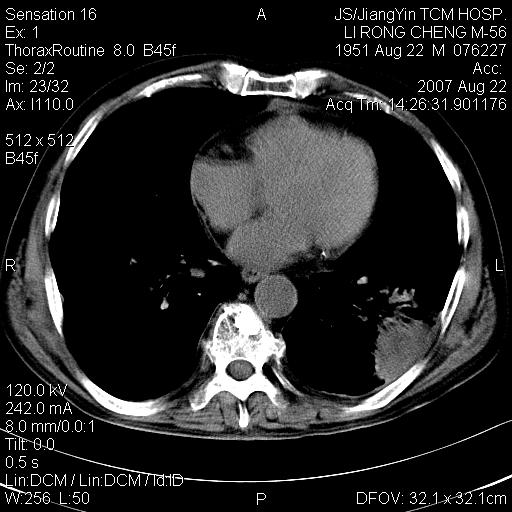

标题: CT9479:M,56Y,DM病史,咳嗽发热5天.肺脓疡.肺癌? [打印本页]

标题: CT9479:M,56Y,DM病史,咳嗽发热5天.肺脓疡.肺癌?

周围有支气管扩张影,伴片块状高密度影,有空洞和胸膜增厚,但是肋骨未见明显破坏,考虑炎性病变可能性大。

左下肺团片状类软组织密度影,形态不规则,边缘欠规整,其内可见液化区及气体影,病灶内侧见引流支气管影,相邻胸膜反应性增厚。病灶周围肺野内见增粗支气管,壁厚,边缘模糊。考虑:支气管扩张并感染;肺脓肿。

支持肺脓肿,左下叶见广泛浸润,并见支扩改变。建议治疗后复查。

考虑左下肺感染,脓肿形成,左下肺支气管扩张,左侧胸膜增厚。其他待排,治疗复查